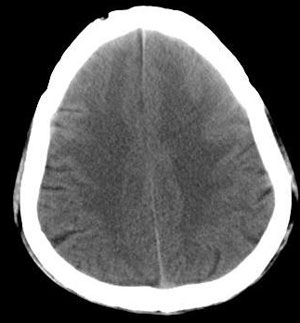

男 54岁 头痛,恶心,患者不同意增强扫描。

左额叶低密度病灶,其前上部分见等高密度影,占位征象明显,首先考虑胶质瘤。又有点象小结节大水肿的转移瘤表现,不知病史多长了,

左侧额叶白质区不规则略高密度影,周围见广泛水肿,左侧脑室受压变形,右侧额叶亦可见一小低密度影,多考虑转移瘤,建议肺部检查

首先考虑转移瘤,查找原发灶,先查肺部,右额叶是不是也有小病灶啊,如不做增强,可做mri。

双侧额叶等低密度灶 左侧有明显占位效应 考虑 转移瘤 可进一步mr检查确诊

左侧额叶不规则等、低混杂密度影,周围见广泛水肿,左侧脑室受压变形,右侧额叶亦可见一小低密度影,多考虑转移瘤,建议作mri检查

左额叶等、高混杂密度片块状病灶,灶周水肿明显,占位效应明显。单看此病灶的确象胶质母细胞瘤,但右额叶、四脑之左后部、脑干亦见数处大小不等片状低密度区,还是首先考虑转移瘤。

左侧额叶不规则略高密度影,周围见广泛水肿,左侧脑室受压变形,多考虑转移瘤,建议进一步检查查找原发灶。

强调前面的战友们提及到的,双侧额叶都有。